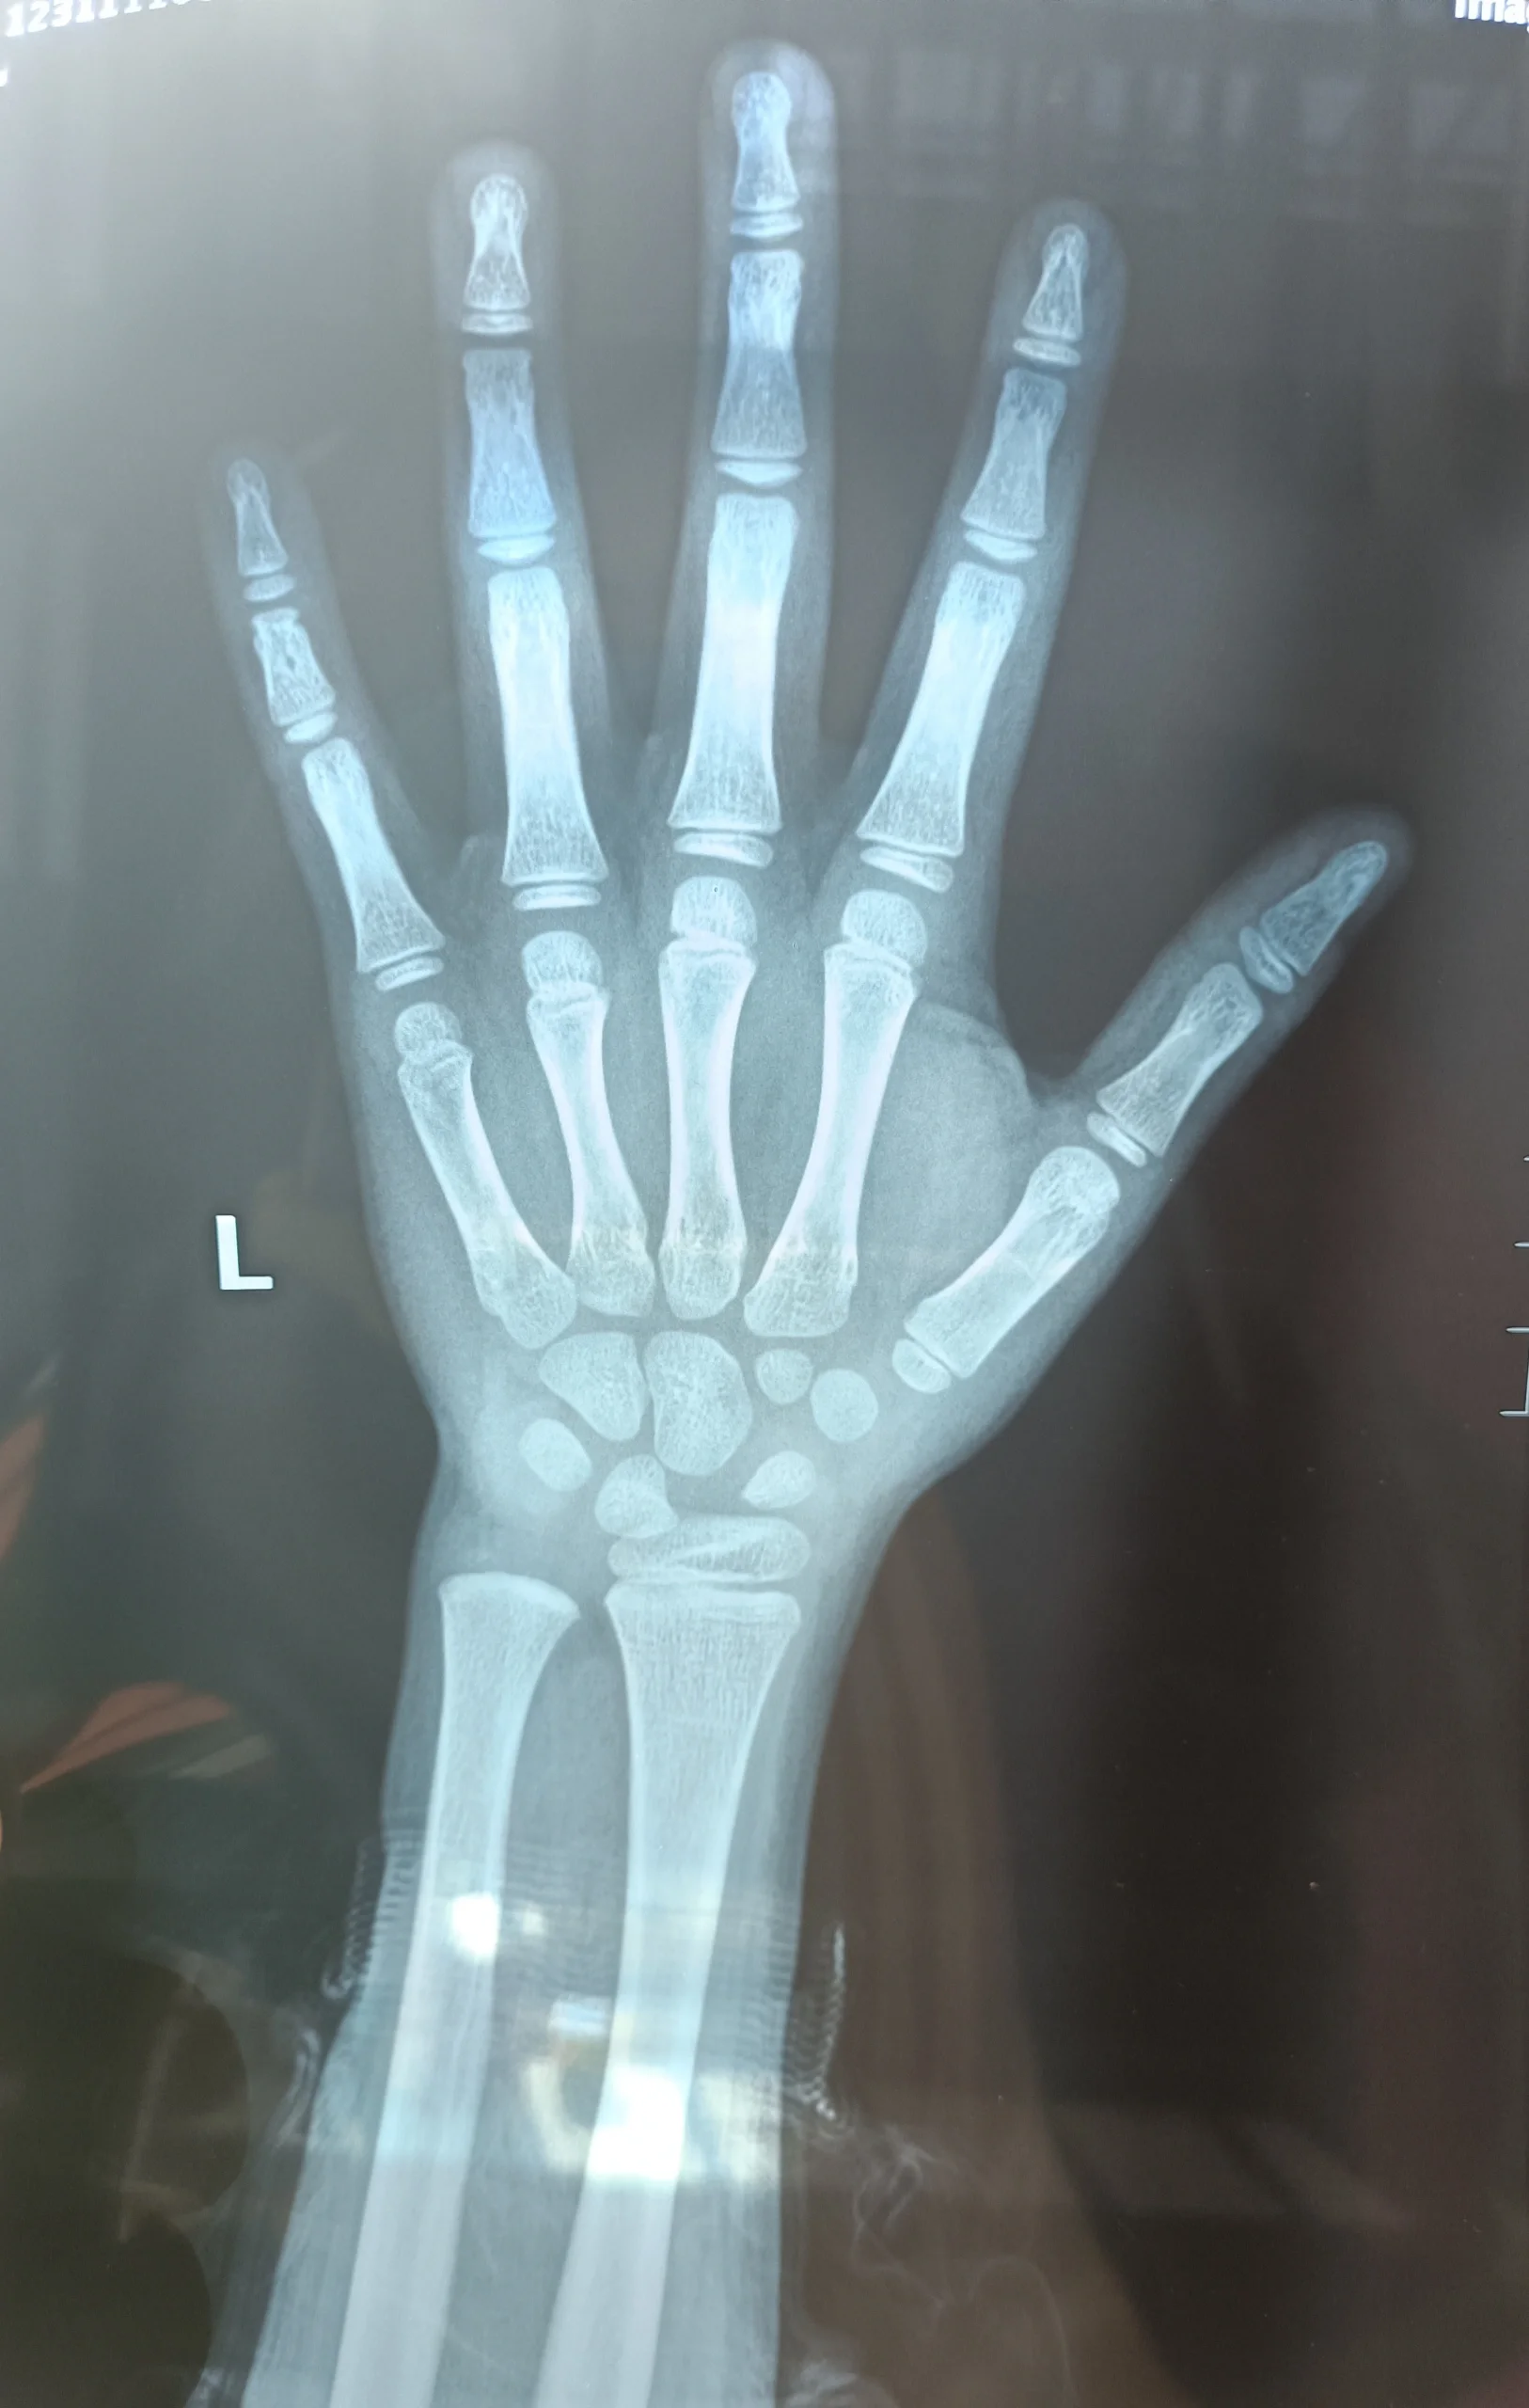

如何提供清晰的骨龄片,确保身高预测准确?

图片尺寸1080x1763